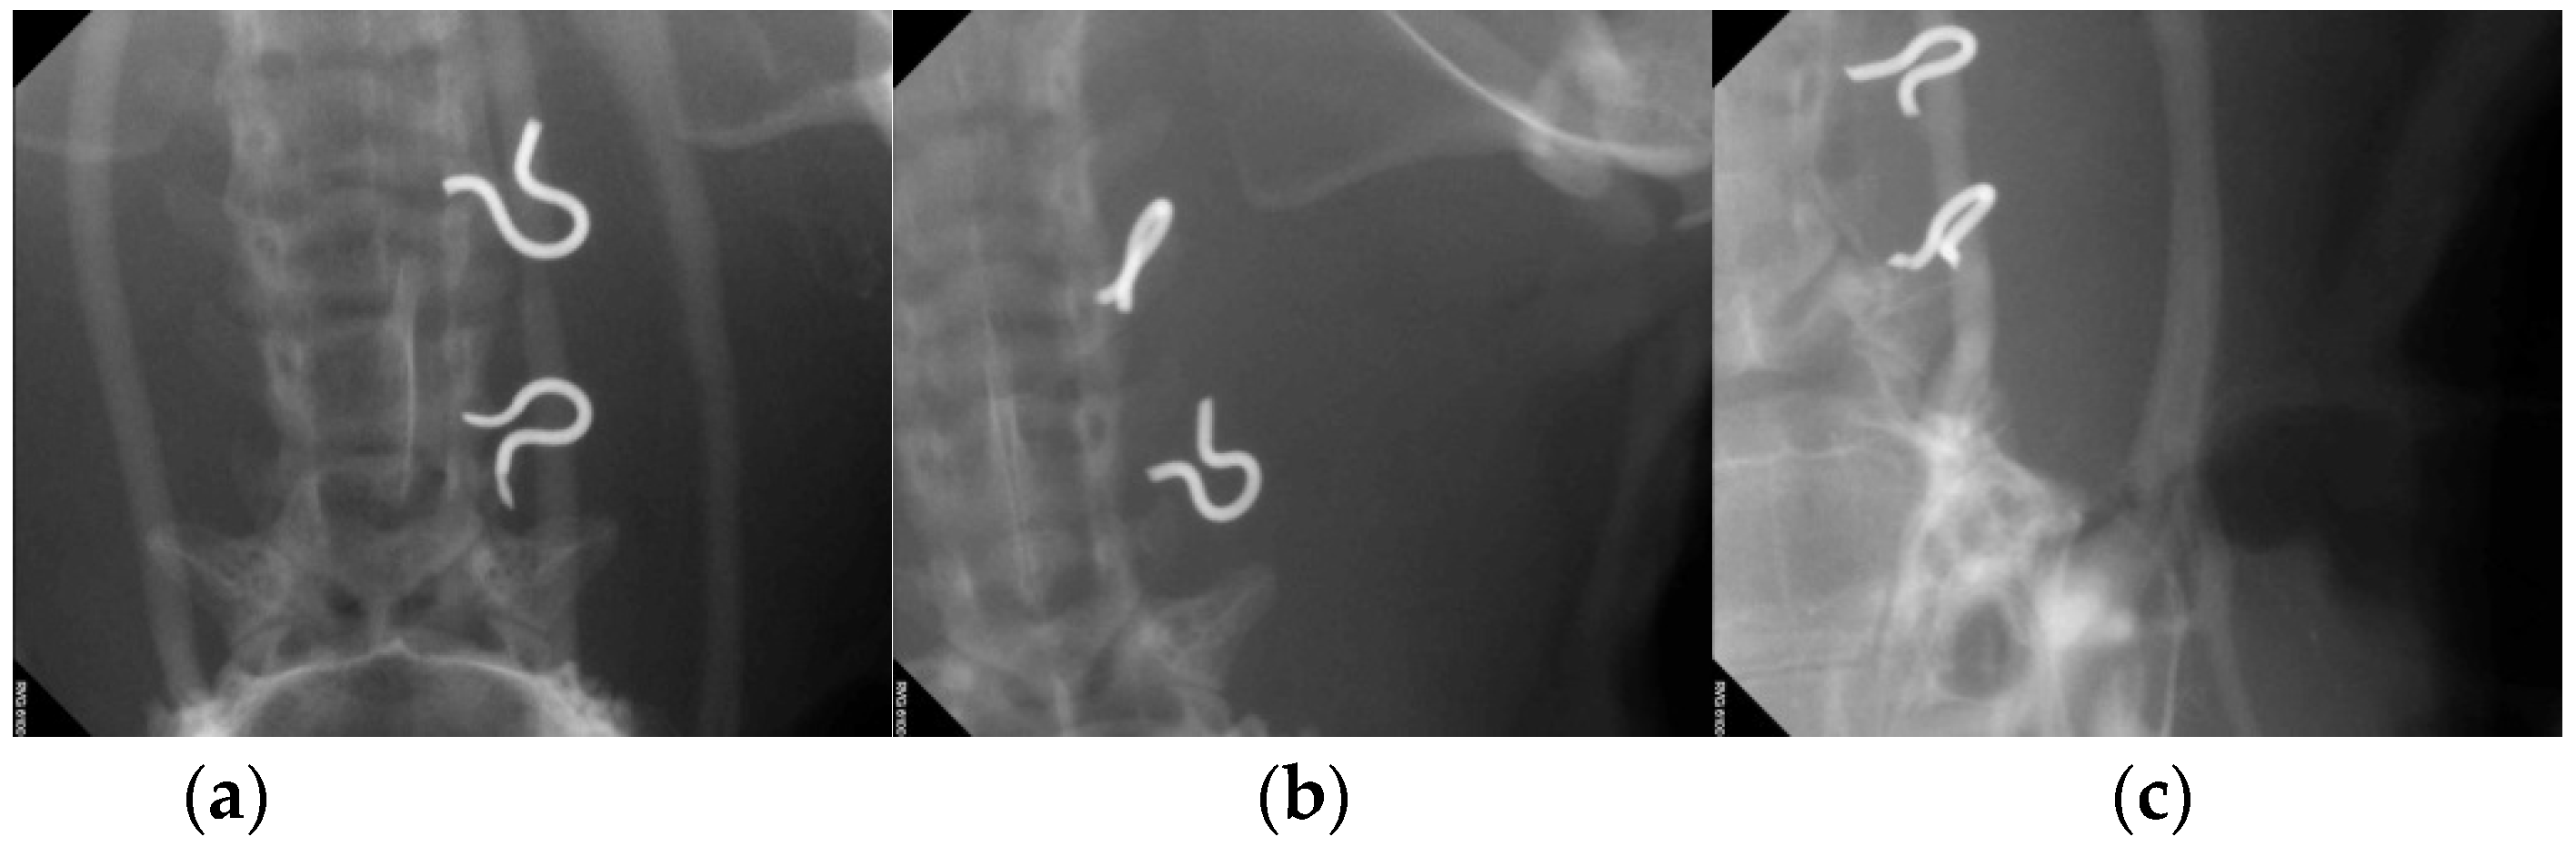

3.4. Artery Patency after Patch Angioplasty